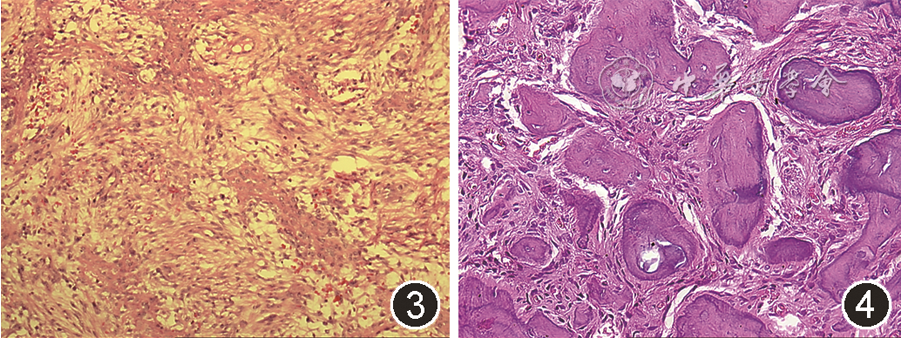

JTOF病变呈黄白色,剖面可见棕色曲线带(brown curvilinear strands)。光镜下见富含梭形细胞的基质与相互连接的幼稚骨小梁相混合,骨小梁周围可见成排的成骨细胞[30](图3)。新形成的类骨质与周围基质界限不清,但随病程进展可通过中心矿化形成编织状骨小梁。基质内可散在破骨细胞样巨细胞灶。水肿、出血、破骨细胞和假囊性基质变性构成了似花环的带状结构,对应着标本剖面特征性的棕色曲线带[31]。

图3 青少年小梁状骨化纤维瘤组织病理学表现(HE染色 低倍放大)

图4 沙瘤样骨化纤维瘤组织病理学表现(HE染色 高倍放大)

病变剖面为黄色粗砂状,光镜下见密集的纤维细胞间质间有大量沙砾体,包含多个不规则球形沙砾样嗜碱性小体,呈同心圆模式嵌在成纤维细胞基质中(图4),晚期可相互融合呈块状,但无明显板层结构。沙砾样小体周围可见嗜酸性边缘,但无成排成骨细胞。尽管细胞较多,但有丝分裂不明显,罕见多核巨细胞[4]。

4. JTOF与PsOF:可根据发病部位、年龄及病理表现鉴别JTOF与PsOF。发病部位方面,额鼻眶筛区PsOF发生率更高;在年龄方面,PsOF在成年人中更常见、年龄分布更广泛、患病年龄较大[(18.9±12)岁],JTOF主要发生于年轻患者[(11.5±6)岁];从病理角度,PsOF内无JTOF特征性的棕色曲线带结构[37]。

此外,COsF中钙化结构常为编织骨和板层骨,周围可见成排的成骨细胞,JTOF中主要为不成熟的骨小梁,周围围绕较大的成骨细胞;而PsOF的钙化结构为特征性的沙砾样小体,周围无成排成骨细胞。